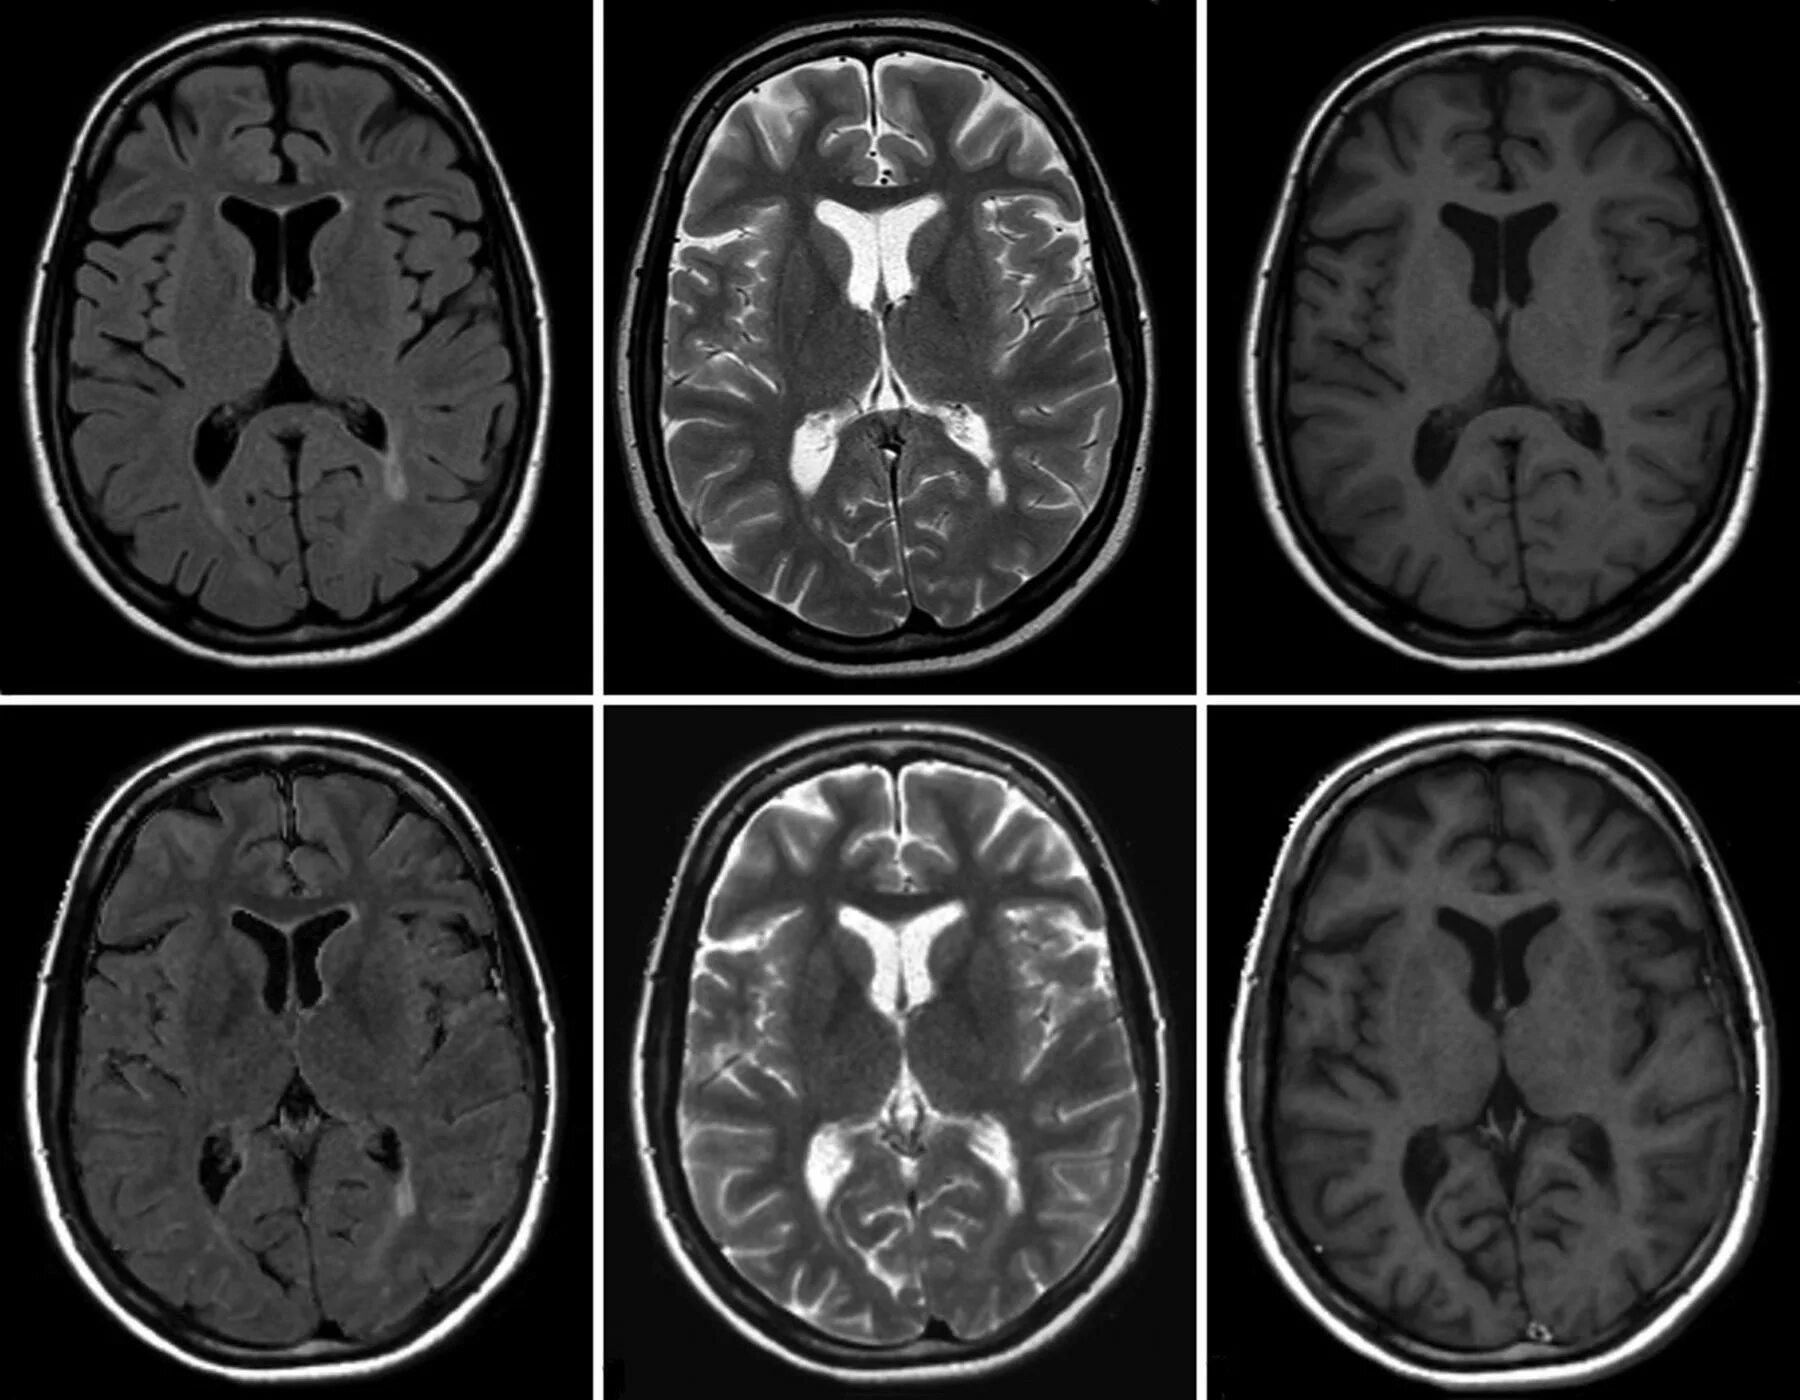

Мрт с контрастированием головного